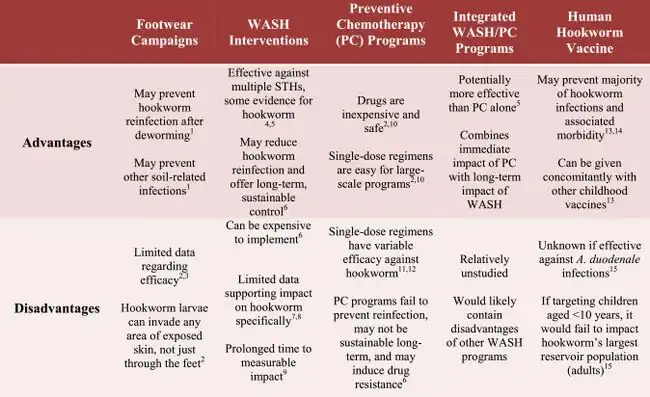

- ↑ Haldeman, Matthew S.; Nolan, Melissa S.; Ng'habi, Kija R. N. (1 January 2020). "Human hookworm infection: Is effective control possible? A review of hookworm control efforts and future directions". Acta Tropica. 201: 105214. doi:10.1016/j.actatropica.2019.105214. ISSN 0001-706X. Archived from the original on 16 April 2024. Retrieved 16 May 2024.